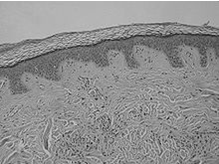

Строение

кожи

Кожа в разрезе

Кожа состоит из эпидермиса, дермы и подкожно-жировой

клетчатки (гиподермы).

§ Дерма, или собственно кожа, представляет собой

соединительную ткань и состоит из 2-х слоев - сосочкового слоя, на котором

располагаются многочисленные выросты, содержащие в себе петли капилляров и

нервные окончания, и сетчатого слоя, содержащего кровеносные и лимфатические

сосуды, нервные окончания, фолликулы волос, железы, а также эластические,

коллагеновые и гладкомышечные волокна, придающие коже прочность и эластичность.